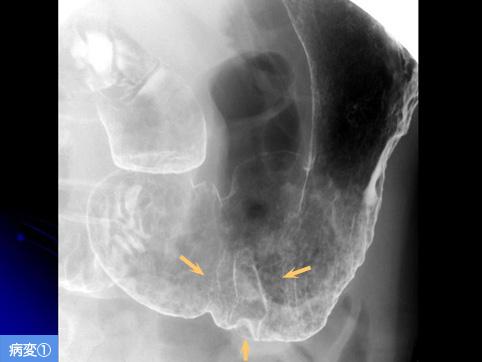

疾患(病理主体)の分類良性上皮性腫瘍/腺腫

部位(臓器別)胃(部位)/前庭

検査方法X-P

腫瘍の肉眼分類0型(表在型)/IIa型(IIa)

病変の最大径(ミリ)20〜24

多発腫瘍(同一臓器)有(同時性)